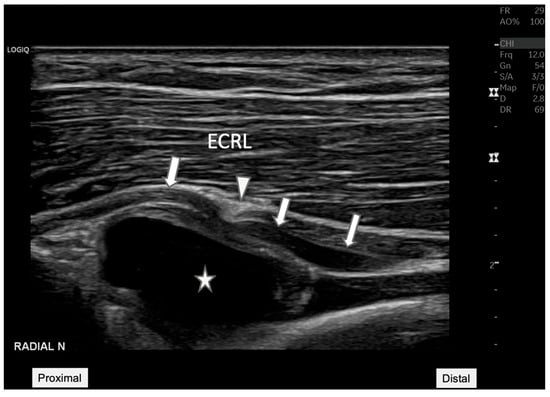

Figure 2. Radial nerve entrapment at the Arcade of Frohse. Longitudinal ultrasound view of the posterior interosseous nerve (arrow) depicting the nerve compression at the Arcade of Frohse (arrowhead). The nerve is visibly constricted by an underlying anechoic cyst (star). This image demonstrates the value of ultrasound in visualizing soft tissue structures, providing essential diagnostic insights into the mechanisms of neuropathic pain and potential therapeutic targets. ECRL: Extensor carpi radialis longus.